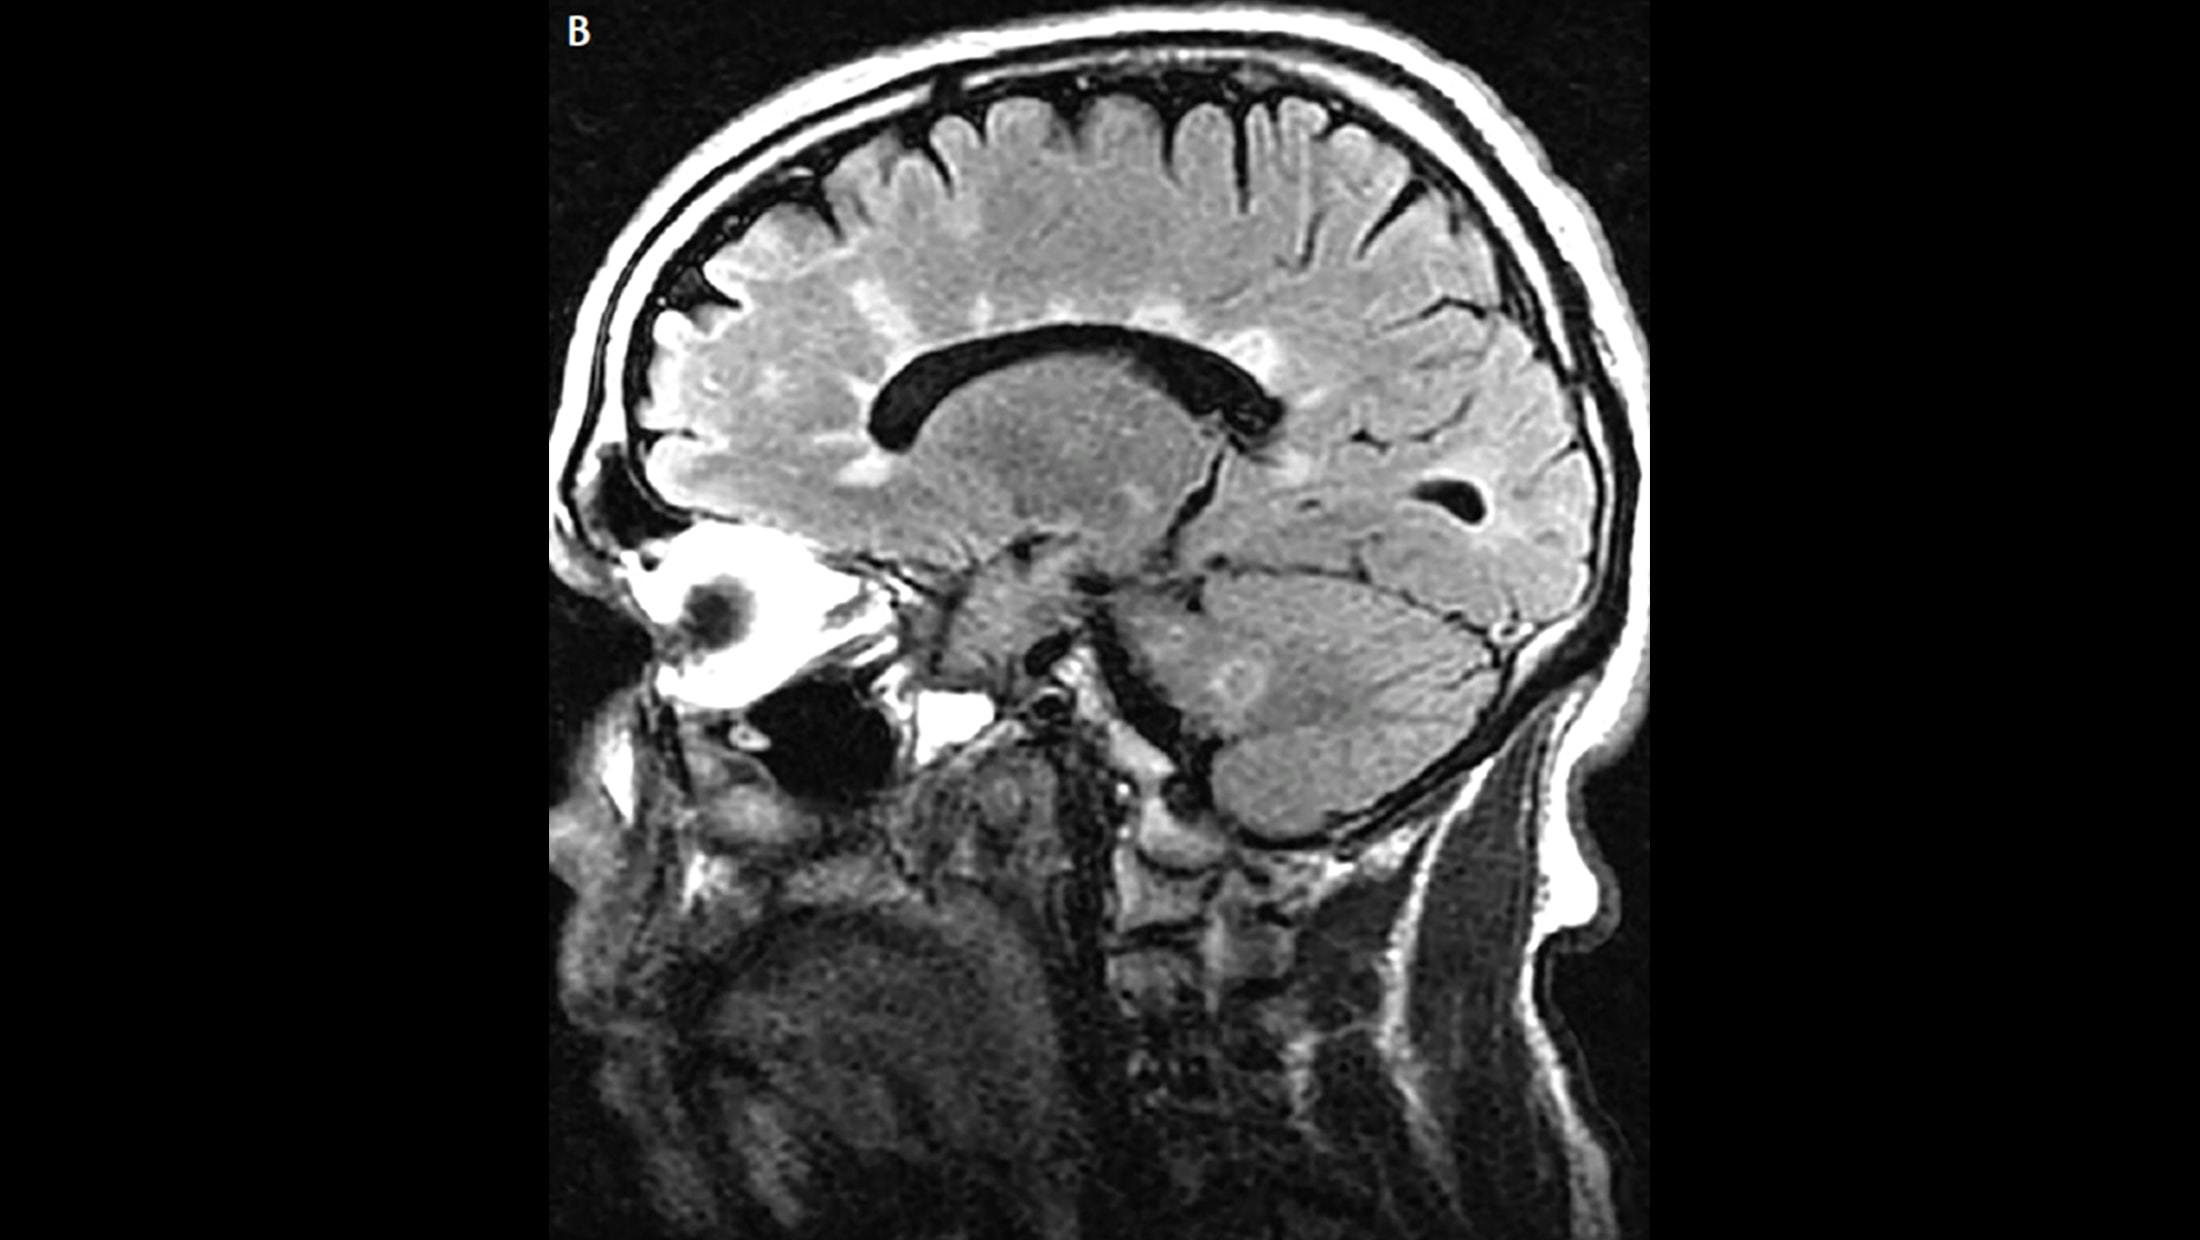

A. Lesions adjacent to lateral ventricle (Dawson’s fingers). MRI from a patient with early MS shows a few Dawson’s fingers on sagittal fluid-attenuated inversion recovery (FLAIR) image.